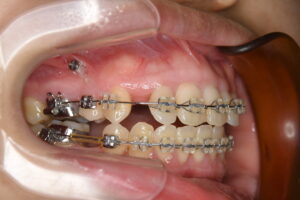

実際の治療経過

初診時の写真

前歯が前にでていて、奥歯しか嚙み合っていないですね。

矯正用のアンカースクリューを入れやすくするために、

歯の根っこの位置を修正するのに一部装置を付けています。

アンカースクリューが入り抜歯しました。

また前歯の突出感も初診時に比べると少し減りましたね!

歯が重なっていて内側に入っていた左上2番目の歯に隙間ができ前に出てきて

ブラケット(歯の正面についている半透明の四角い装置)が付けれるようになりました。

左右3番目の歯が後ろにつくくらいまで下がったのでこれから前歯をさげる準備に入ります!!

こちらが現在のものになります。